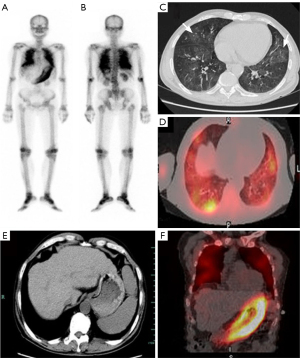

Based on the clinical presentation of hypercalcemia with suppressed PTH and the absence of malignancy evidence on the initial workup, Tc-99m MDP SPECT/CT was performed to exclude occult osteolytic metastases and evaluate metastatic calcifications resulting from calcium-phosphate dysregulation. A Tc-99m MDP SPECT/CT scan (740 MBq [20 mCi], imaging at 180 minutes post-injection) demonstrated increased tracer uptake in the stomach and lungs (Figure 1), indicative of extensive metastatic calcification. Chest computed tomography (CT) showed bilateral pulmonary exudative changes and mildly enlarged lymph nodes in the axillary and mediastinal regions, suggestive of inflammation; thus, empiric anti-infective therapy was initiated.

To confirm the diagnosis, bronchoscopy and lymph node biopsy were performed. The bronchoscopic evaluation revealed chronic inflammation with eosinophil infiltration and diffuse mucosa microcalcifications (Figure 2). Histopathology of the left axillary lymph node excluded hematologic malignancy, but showed prominent IgG4-positive plasma cell infiltration [approximately 40 per high-power field (HPF)], IgG4+/IgG+ ratio >40% (Figure 2). The bone marrow biopsy showed markedly reduced hematopoietic hyperplasia, with the intramedullary hematopoietic component accounting for approximately 20% of the cellularity. Microscopic examination demonstrated the presence of granulocytic, erythroid, and megakaryocytic lineages, accompanied by abundant eosinophilic infiltration and scattered lymphoplasmacytic cells. Immunohistochemical staining showed diffuse positivity for IgG and focal positivity for IgG4. The renal biopsy findings demonstrated global glomerulosclerosis in approximately 25% of glomeruli and multiple microcalcifications within renal tubular epithelial cells. Multifocal plasma cell infiltration and fibrous tissue hyperplasia were observed in the renal interstitium. Electron microscopy revealed diffuse and irregular thickening of the basement membrane, occasional electron-dense deposits in the mesangial region, and the widespread effacement of the podocyte foot processes. Immunostaining highlighted abundant IgG4-positive plasma cell infiltration (>10 per HPF). Collectively, these features fulfilled the diagnostic criteria for immunoglobulin G4-related tubulointerstitial nephritis (IgG4-TIN).